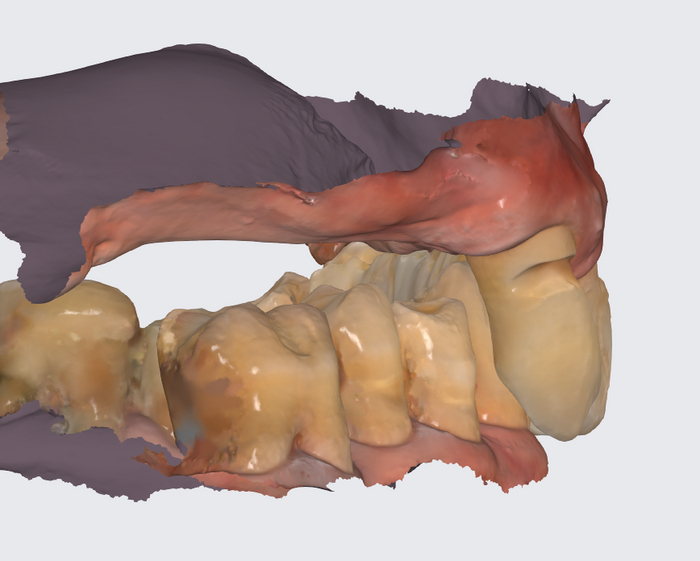

А теперь посмотрим на картину с антагонистами.

Важно - мы не переделывали прикус! А повторили тот, что у пациента уже был, только высоту вернули.

Проверяем попадание в прикус.

Временный протез "всё на 4-х", постановка на воске

На фото выше - воск. Протез временный будет поизящнее. Постоянный, когда до него дойдёт, ещё более гладкий и аккуратный получится.